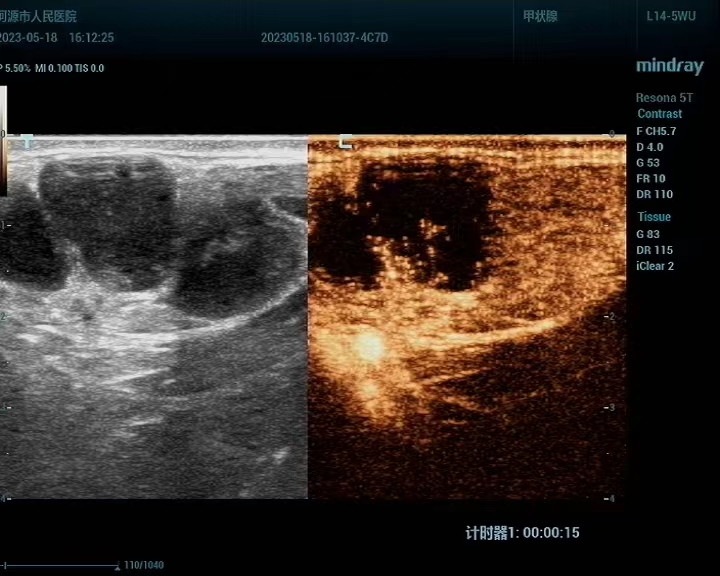

术前超声造影评估淋巴结坏死区域

这两位患者中,一位是因为腋下有肿物前来我院就诊;另一位是因为颈部出现肿物想完善检查和治疗。超声检查均提示为多发淋巴结肿大。门诊医生看过超声结果后,表示可以做超声引导下穿刺活检对淋巴结肿大病因进行进一步的明确诊断,所以两位患者来到我科了解相关内容。我科介入团队医师接诊两名患者后,通过分析常规超声结果,针对淋巴结可能存在坏死灶的情况,建议患者先做超声造影。造影评估发现,淋巴结内存在多处坏死,因此在术中介入团队医师们精准地避开了淋巴结的坏死区域,在尽量减少穿刺次数避免损失的原则上取出了有意义的组织。超声介入团队的陈俏伟医师、陈钦主治医师和徐小嫣护理师在超声医学科负责人高兴副主任医师的现场指导下,成功做到了术前有效评估,术中安全疼痛感轻微,术后无并发症。